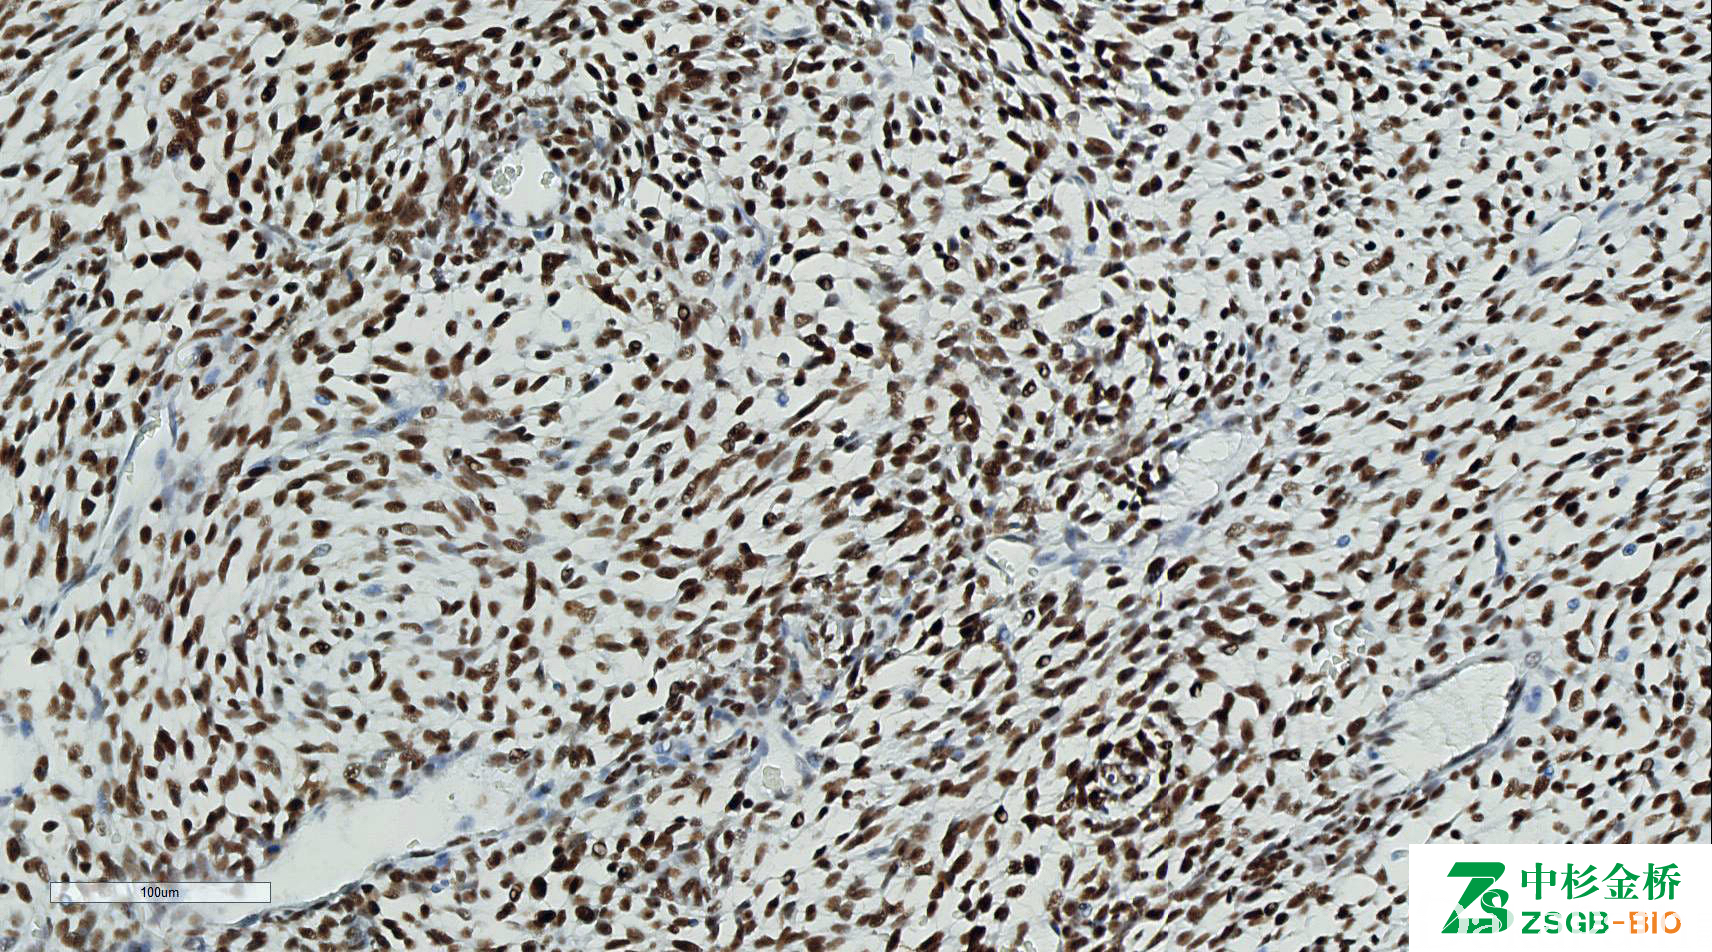

TLE1

信号定位: 胞核

对滑膜肉瘤的诊断敏感性达到 82%,特异性 92%,用于滑膜肉瘤的诊断,与 EMA、BCL2、AE1/AE3 联用对诊断滑膜肉瘤特异性及敏感性均很高。但热修复会导致非特异性着色。